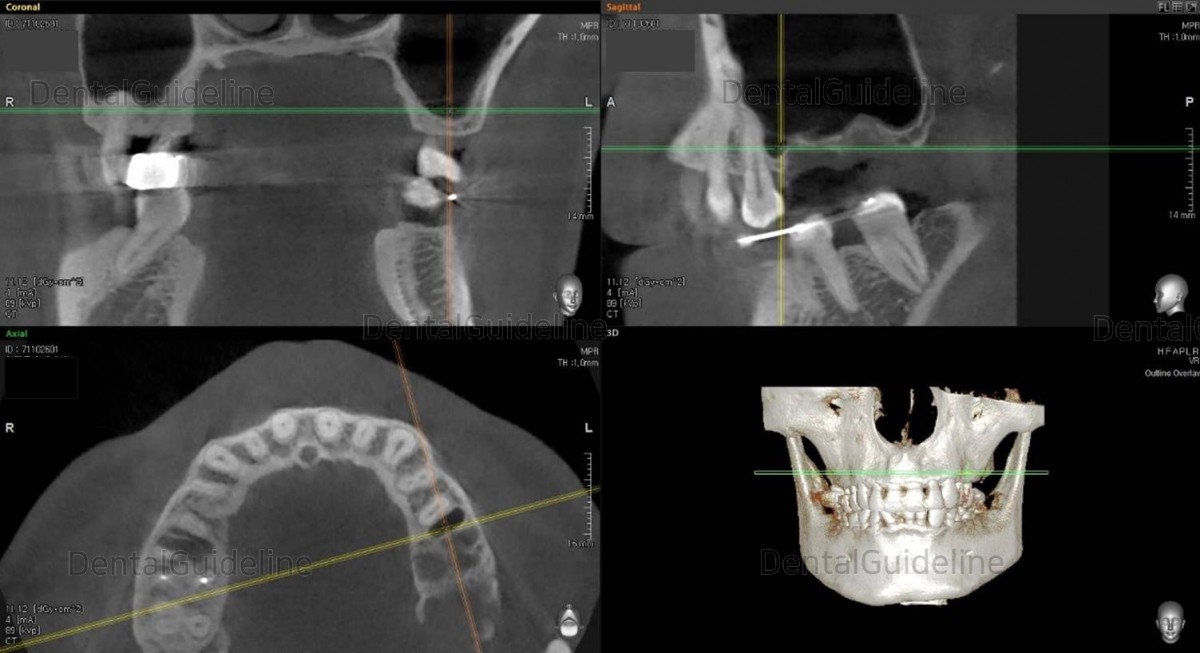

2. CBCT radiograph showed that the inflammation had already spread to the maxillary sinus, and the apical lesion was also seen in the first molar.